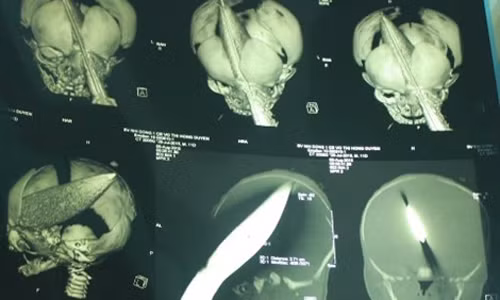

| Bé trai 11 ngày tuổi bị đâm xuyên sọ ngay tại bệnh viện. |